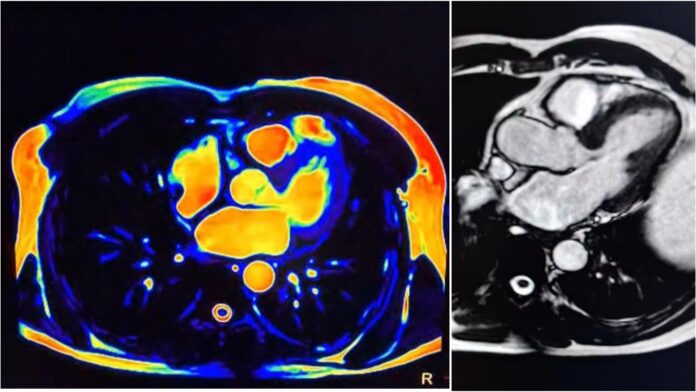

Cos’è e a cosa serve la Risonanza magnetica cardiaca?La Risonanza magnetica al cuore (Rm o Rmn cardio) è un esame di secondo livello che sfrutta i campi magnetici (non usa i raggi X, non vi è presenza di radiazioni ionizzanti) e grazie a questi è in grado di far emergere la presenza di eventuali danni al cuore, sia recenti sia cronici. Per questo motivo è utile nella diagnosi e cura in ambito cardiologico. Si può effettuare con o senza mezzo di contrasto e con o senza sedazione del paziente. L’esame trova applicazione in tutte le patologie cardiache e in molti casi viene considerato indispensabile. È l’ennesimo servizio che la nota clinica della Riviera dei Cedri offre ai pazienti per ampliare la propria offerta sanitaria.